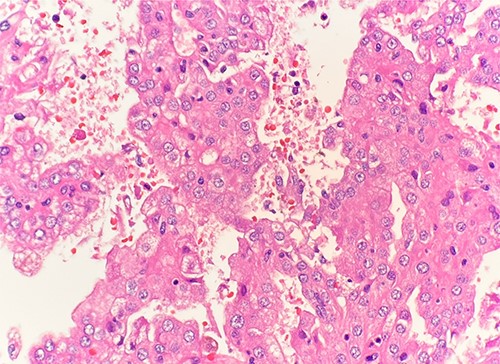

Microscopic examination revealed that clear cell RCC (Fig. 1), papillary RCC type 1 (Fig. 2), and papillary RCC type 2 (Fig. 3) were present in the right kidney, and papillary RCC type 2 was present in both kidneys. Immunostaining showed that tumor cells were positive for alpha-methyacyl-CoA racemase (Fig. 4), CD10, CK7, and vimentin, and negative for CD117.

Microscopic examination reveals pseudostratified tumor cells with papillary architecture, abundant eosinophilic, atypical nuclei and prominent nucleoli. HE stain 40x.